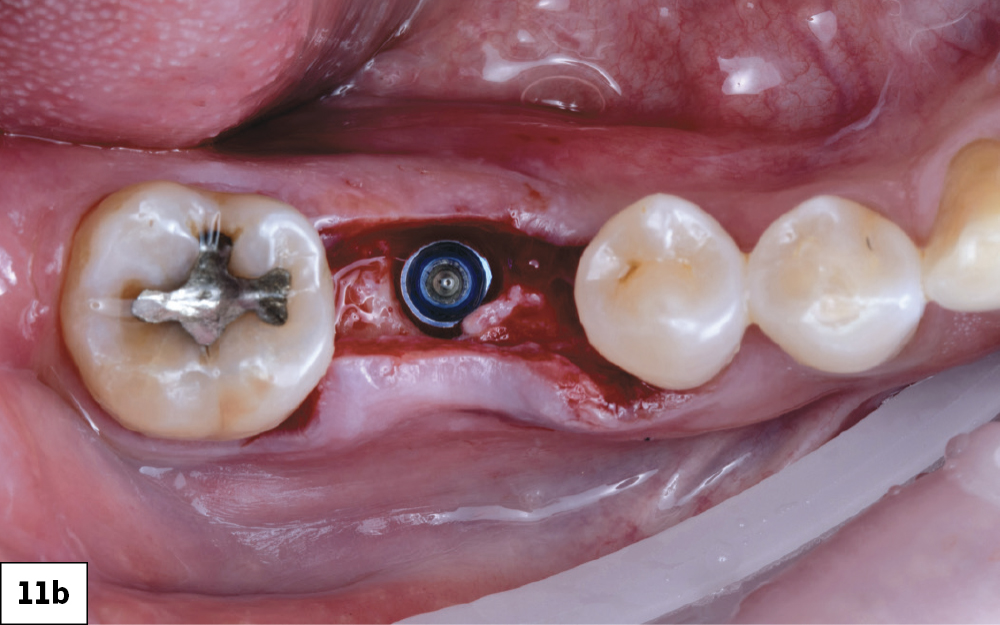

Implant Torqued to 35 Ncm

Glidewell Custom Healing Abutment Fully Seated

Figures 11a–11c: A 5 x 11.5 mm Glidewell HT Implant was placed into the fully prepared osteotomy. The implant was torqued to 35 Ncm. A Glidewell custom healing abutment was fully seated and the soft tissue approximated over the ridge. The custom healing abutment was chosen to guide gingival healing for an ideal esthetic outcome.